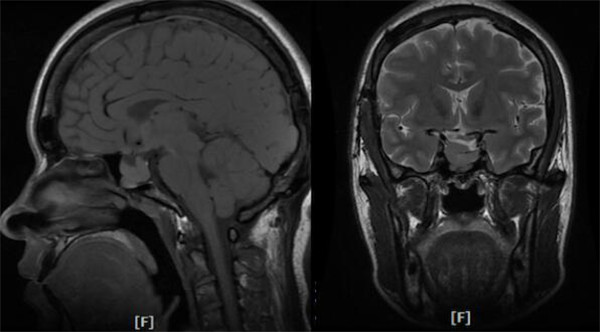

头颅MRI示肿瘤主体位于鞍内,质地硬韧,与颈内动脉粘连紧密

垂体动态增强示右侧鞍上池受压上抬,鞍隔显示不清,肿瘤不均质增强